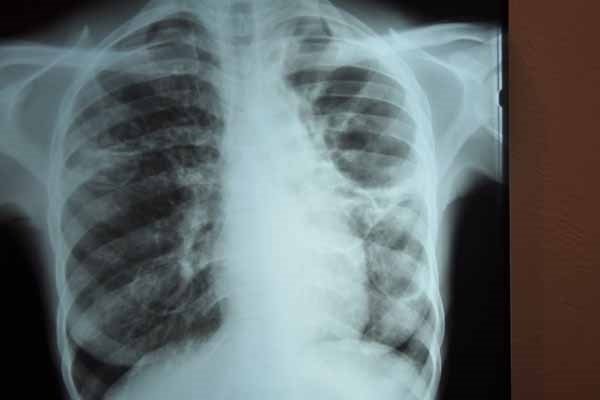

Radyolojik tetkiklerde (CT, MR, PET) kanserden şüphelenildiği taktirde dokudan küçük parça almak için biyopsi işlemi yapılmalıdır. Bu işlem farklı yöntemlerle olmaktadır. Bazı hastalarda iğne ile dışarıdan girerek, bazı hastalarda ise bronkoskopi bir cihazla endoskopik olarak yapılmaktadır. Bronkoskopide ultrason ve ultrasonsuz olarak iğne ve penslerle hastalar uyutularak biyopsi yapılmaktadır

Kanser hücreleri dokuda tespit edildiğinde en uygun tedaviyi planlamak için genetik analiz yapılmaktadır.

İki ana tıp vardır. Küçük hücreli ve küçük hücreli dışı akciğer kanserleri. Evreleme ise kanserin yayılması ve büyüklüğü ile doğru orantılıdır.